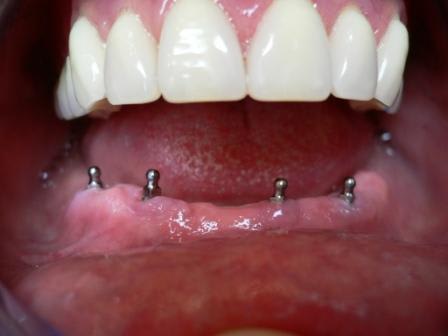

Ci-joint qq images de mon dernier petit All-on-"FOUR" qui date de la semaine dernière.

P1000812 gqllw9 - Eugenol

P1000663 t3yc0w - Eugenol

P1000816 mchm9u - Eugenol

009 fx01gm - Eugenol

024 vownvo - Eugenol